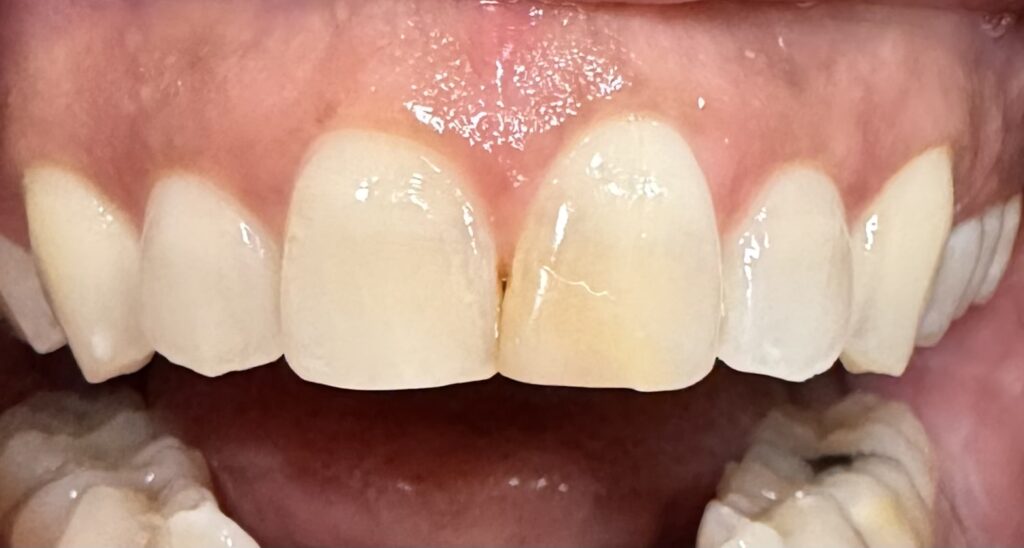

The Challenge The patient arrived at Serenity Dental Spa with a single, pronounced source of self-consciousness: a discolored and noticeable composite filling on a prominent